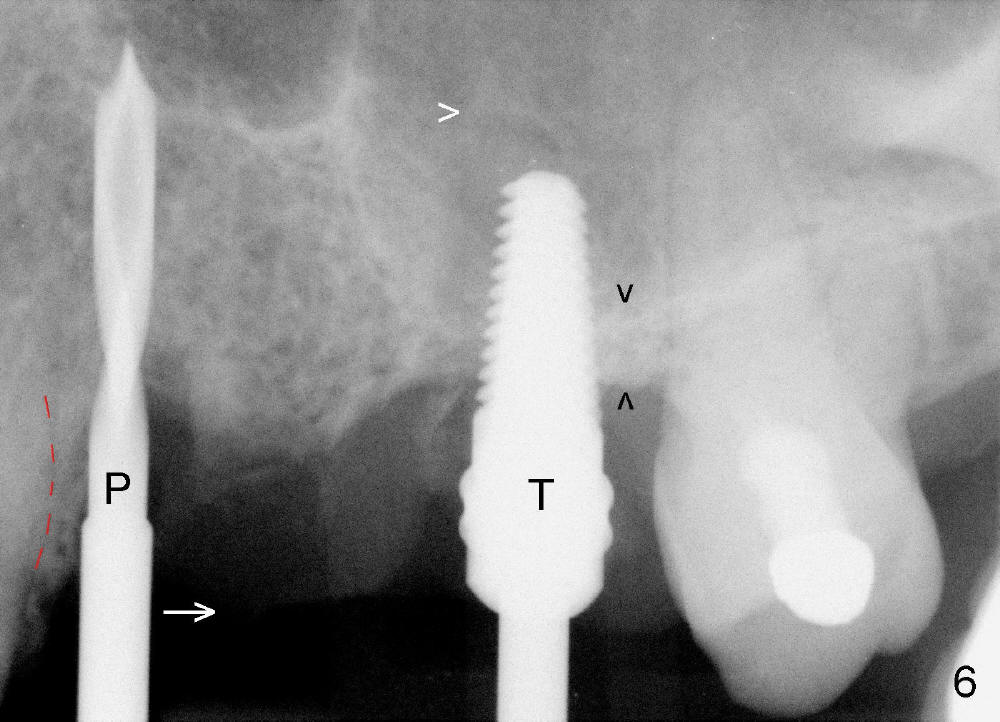

Initially the osteotomy is established with drill/reamers alternated with taps in the septum near the palatal socket. When a 4.5x14 mm tap (Fig.6 T; Fig.7: #14) is inserted, the sinus floor is perforated, but the sinus membrane is intact. When 7x14 mm tap is inserted, the sinus membrane is perforated in the buccal aspect of the osteotomy. The latter is repaired by placement of collagen dressing and then bone graft and membrane again (sandwich). The osteotomy is shifted to the palatal socket by using 5x14 and 6x14 mm taps. When the last tap is removed, the small area of the buccal aspect of the osteotomy is also found to be perforated, but the membrane is intact. When a 6x14 mm implant is placed (Fig.8), the coronal end is close to the middle of the socket (buccopalatally, due to angulation of the palatal socket).

Placement of immediate implant at the site of #12 is relatively easy. Adjustment is more or less mesiodistal. A 2 mm pilot drill (Fig.6 P) is found close to the root of the tooth #11 (red dashed line). The osteotomy is then moved distally (Fig.6 arrow). When 4.5x20 mm tap (Fig.7: #12) and 4.5x17 mm implant (Fig.8 I) are placed, there is distance from the root of the neighboring tooth. Insertion torque of the both implants is >60 Ncm. Abutments are placed (A in Fig.8) for immediate provisional.